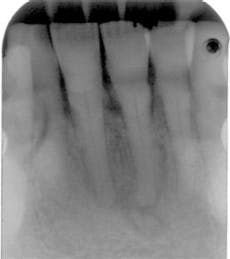

Often, the periapical cemento-osseous dysplasia can be followed when the patient is seen periodically over a long period of time. The second image presented here occurred over a 23-year period with observation (see Figure 2).